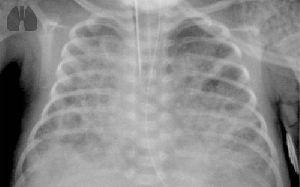

Chronic obstructive pulmonary disease (COPD) which comprises the phenotypes of chronic bronchitis and emphysema is often associated with pulmonary hypertension (PH). However, currently no approved therapy exists for PH-COPD. Signalling of the nitric oxide/cyclic guanoside monophosphate (NO-cGMP) axis plays an important role in PH and COPD.

We investigated the treatment effect of riociguat, which promotes the NO-cGMP pathway, in the mouse model of smoke-induced PH and emphysema in a curative approach and retrospectively analysed the effect of riociguat treatment on PH in single patients with PH-COPD.

In mice with established PH and emphysema (after 8 months of cigarette smoke exposure) riociguat treatment for another 3 months fully reversed PH. Moreover, histological hallmarks of emphysema were decreased. Microarray analysis revealed involvement of different signalling pathways, e.g. related to matrix metalloproteinases (MMPs). MMP activity was decreased in vivoby riociguat. In PH-COPD patients treated with riociguat (n=7) the pulmonary vascular resistance, airway resistance and circulating MMP levels decreased, while oxygenation at rest was not significantly changed.

Conclusions: Riociguat may be beneficial for treatment of PH-COPD. Further long-term prospective studies are necessary to investigate the tolerability, efficacy on functional parameters and the effect specifically on pulmonary emphysema in COPD patients.